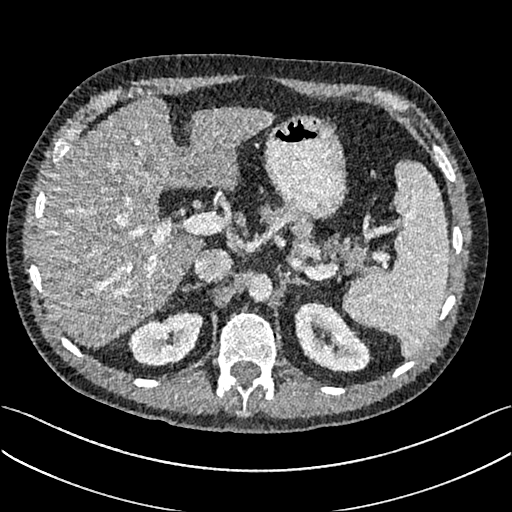

To show the denoising effect of the selected networks, we took two representative slices as shown in Figs. 5 and 7. And Figs. 6 and 8 are the zoomed regions-of-interest (ROIs) marked by the red rectangles in Figs. 5 and 7. All the networks demonstrated certain denoising capabilities. However, CNN-MSE blurred the images and introduced waxy artifacts as expected, which are easily observed in the zoomed ROIs in Figs. 6e and 8e. WGAN-MSE was able to improve the result of CNN-MSE by avoiding over-smooth but minor streak artifacts can still be observed especially compared to CNN-VGG and WGAN-VGG. Meanwhile, using WGAN or GAN alone generated stronger noise (Figs. 6g and 8g) than the other networks enhanced a few white structures in the WGAN/GAN generated images, which are originated from the low dose streak artifact in LDCT images, while on the contrary the CNN-VGG and WGAN-VGG images are visually more similar to the NDCT images. This is because the VGG loss used in CNN-VGG and WGAN-VGG is computed in a feature space that is trained previously on a very large natural image dataset [48]. By using VGG loss, we transferred the knowledge of human perception that is embedded in VGG network to CT image quality evaluation. The performance of using WGAN or GAN alone is not acceptable because it only maps the data distribution from LDCT to NDCT but does not guarantee the image content correspondence. As for the lesion detection in these two slices, all the networks enhance the lesion visibility compared to the original noisy low dose FBP images as noise is reduced by the different approaches.

As for iterative reconstruction technique, the reconstruction results depend greatly on the choices of the regularization parameters. The implemented dictionary learning reconstruction (DictRecon) result gave the most aggressive noise reduction effect compared to the network outputs as a result of strong regularization. However, it over-smoothed some fine structures. For example, in Fig. 8, the vessel pointed by the green arrow was smeared out while it is easily identifiable in NDCT as well as WGAN-VGG images. Yet, as an iterative reconstruction method, DictRecon has its advantage over post-processing method. As pointed by the red arrow in Fig 8, there is a bright spot which can be seen in DictRecon and NDCT images, but is not observable in LDCT and network processed images. Since the WGAN-VGG image is generated from LDCT image, in which this bright spot is not easily observed, it is reasonable that we do not see the bright spot in the images processed by neural networks. In other words, we do not want the network to generate structure that does not exist in the original images. In short, the proposed WGAN-VGG network is a post-processing method and information that is lost during the FBP reconstruction cannot easily be recovered, which is one limitation for all the post-processing methods. On the other hand, as an iterative reconstruction method, DictRecon algorithm generates images from raw data, which has more information than the post-processing methods.